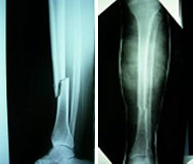

Fracturas de tibia y peroné

La región de la pierna engloba las diáfisis o zonas centrales de la tibia y el peroné. Son las fracturas de huesos largos (fémur, tibia, húmero, cúbito y radio) más frecuentes en el adulto y pueden producirse por un impacto directo (accidentes de tráfico, caídas desde gran altura, deportes de contacto o de motor) o por un mecanismo indirecto (torsión de la pierna en deportes de salto o sobrecarga repetida en bailarines y reclutas). El tratamiento varía en función del desplazamiento y el grado de afectación de la musculatura y piel circundante. El avance en las técnicas quirúrgicas ha permitido, cuando la indicación lo requiere, el empleo de una cirugía mínimamente invasiva que permite reparar grandes fracturas a través de mínimas heridas disminuyendo la agresión al tejido y favoreciendo la rápida incorporación a la actividad diaria.